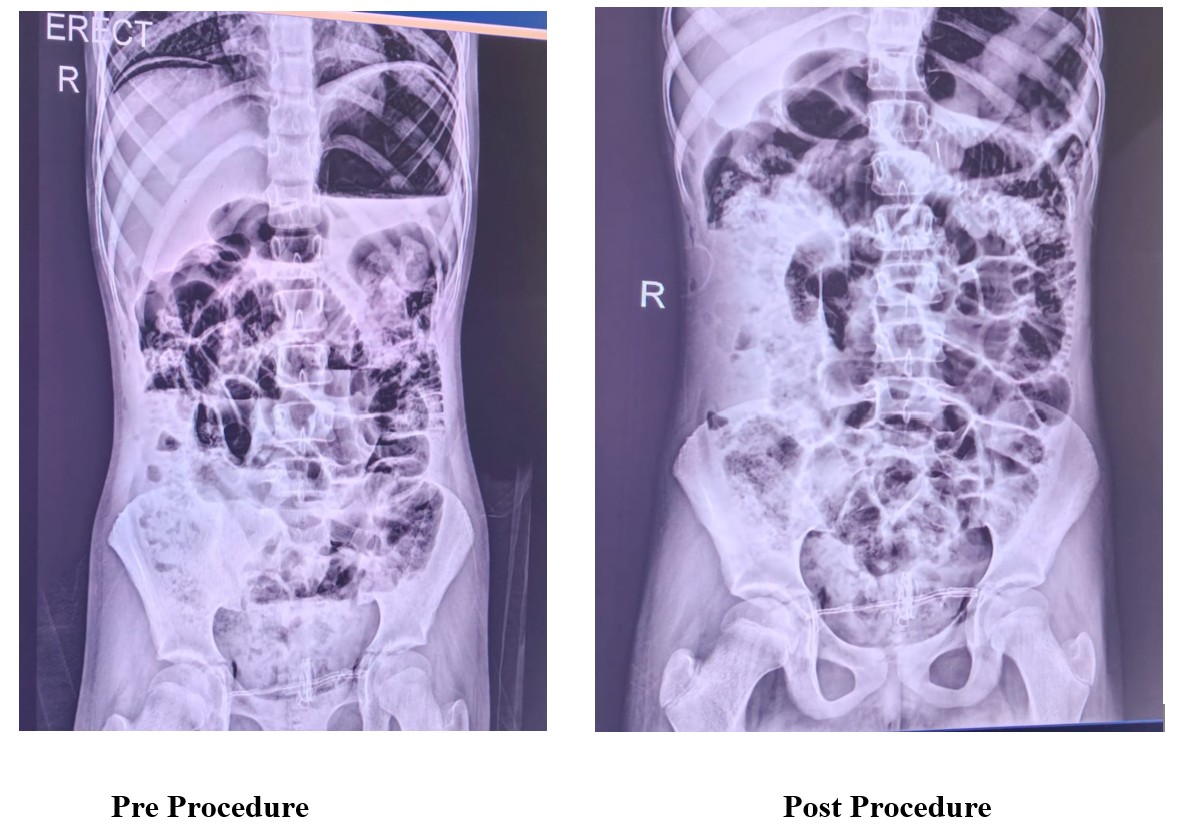

Pre-operative investigations included a failed endoscopic removal attempt on 26 October 2025, which confirmed the presence of a large amount of hair causing gastric outlet obstruction. The pre-operative diagnosis was Gastric Bezoar (Trichobezoar).

Given the size and extent of the mass, and the failure of endoscopic removal, definitive surgical management was indicated. The procedure was performed on 04 November 2025 under General Anaesthesia (GA).

Intraoperative findings confirmed the diagnosis, revealing a massive trichobezoar occupying the entire stomach and extending into the duodenum, resulting in partial gastric outlet obstruction.

The surgical approach utilized standard laparoscopic access, including a 10mm infraumbilical port and an 8.5mm right hypochondrium (RH) port. A gastrostomy was executed on the anterior gastric wall using a monopolar hook. The surgical team successfully retrieved the entire trichobezoar out of the stomach. To minimize fascial disruption during specimen removal, the mass was extracted through a 5mm supra-pubic Pfannenstiel incision. Following retrieval, the gastrostomy site was closed in two layers (sutures using MAXON 2-0 and Prolene 2-0). The abdomen was subjected to Normal Saline (NS) wash before closure.

This case successfully demonstrates the feasibility of laparoscopic gastrostomy and retrieval for massive gastric bezoars. By utilizing a small supra-pubic Pfannenstiel incision solely for specimen extraction, the morbidity associated with traditional midline open gastrotomy was avoided, contributing to the patient’s rapid return to oral intake and stable discharge within six days.